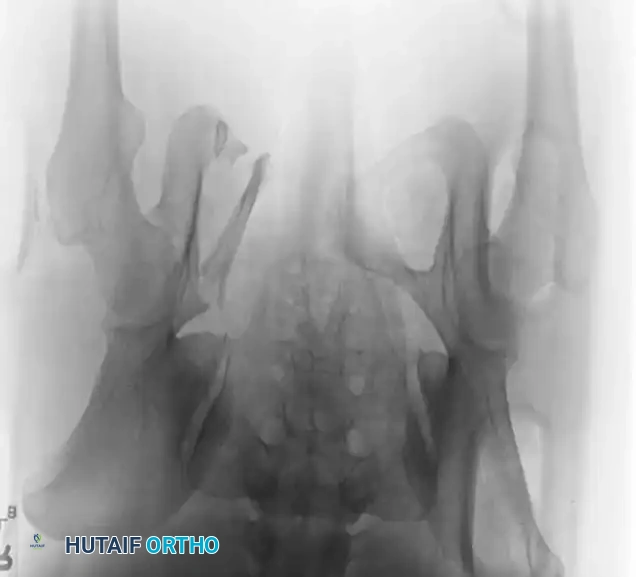

Radiographic Evaluation

Standard evaluation begins with an Anteroposterior (AP) pelvis radiograph. However, definitive surgical planning requires specialized views and advanced imaging.

• Inlet View: Directed 45 degrees caudad. Best evaluates anterior-posterior translation, internal/external rotation, and sacral impaction.

• Outlet View: Directed 45 degrees cephalad. Best evaluates vertical translation and sacral foraminal anatomy.

• CT Scan: The gold standard for evaluating posterior ring injuries, sacral dysmorphism, and preoperative planning for percutaneous fixation.